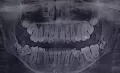

Здравствуйте! Треснул зуб 7-ка. Он был депульпирован, каналы запломбированы 6 лет назад. Откололась примерно 1/3, она в десне и шатается, вторая часть стоит крепко. Есть ли какое-то временное решение, так как сейчас нахожусь не дома и к своему стоматологу смогу попасть только через 1-2 месяца. Спасибо!

Если стенка сломалась под десну, то к сожалению такой зуб удаляется. Так что не тяните и не терпите боль, обратитесь к врачу и если мое предположение подтвердится то удалите зуб.